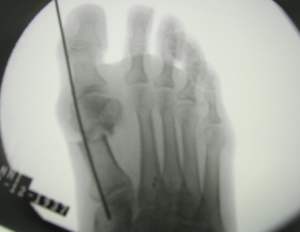

Si taglia l’osso

Una immagine radiografica dopo aver tagliato l’osso e aver posizionato il filo di tenuta